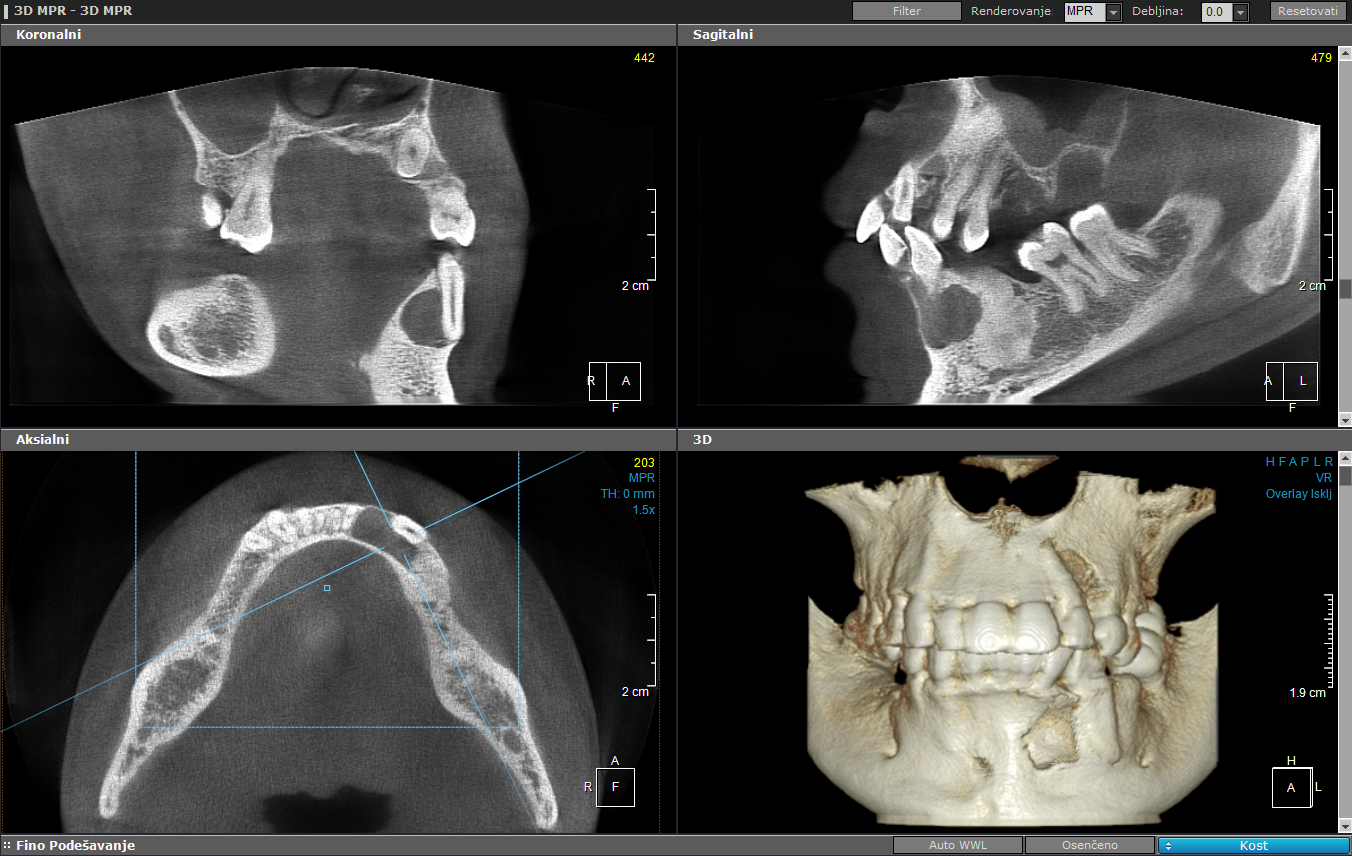

У оквиру софтвера се добија радиолошки и дентални модул са опцијом планирања имплантата и базом свих тржишно доступних имплантата.

6x4цм, стандардна резолуција

6х8см, висока резолуција

11x8цм, стандардна резолуција